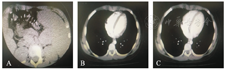

患儿,男,10岁,以"乏力、间断排黑便20余天,呕血1 d"为主诉入院。患儿于入院前20余天出现头晕、乏力、间断排黑便,就诊于当地医院,诊断为"贫血",经输血、补铁等对症治疗1周后患儿好转出院。于入院前1 d无明显诱因出现呕血,共计3~4次,呕血量400~500 mL,状态差,遂急诊入我科抢救治疗。病程中无发热,无腹痛,无腹泻,尿量及尿色正常。患儿既往体健,无特殊用药病史及不洁饮食史。入院查体:体温36.8 ℃,脉搏114次/min,呼吸24次/min,血压98/58 mmHg(1 mmHg=0.133 kPa);一般状态差,精神萎靡;皮肤、结膜及口唇苍白,全腹软,上腹部压痛,无反跳痛、肌紧张;脾脏左肋下约2 cm,质地韧,边钝;肺部、心脏、神经系统查体未见异常。血常规:红细胞2.37×1012/L,血红蛋白55 g/L,红细胞比容0.189,网织红细胞百分比7.63%;血细胞形态:成熟红细胞大小不等。PCT 0.21 ng/mL(参考值0~0.5 ng/mL)。入院后初步诊断为重度贫血,上消化道出血,给予输血、禁食、补液等对症支持治疗。患儿生命体征平稳后,陆续完善检查以明确上消化道出血的原因。腹部超声:胰尾区探及大小46 mm×36 mm的低回声,边界欠清,内部回声不均匀,可见血流信号,与胰尾分界不清。脾厚39 mm,肋弓下24 mm。消化道内镜检查:胃体胃底大弯侧可见数条迂曲的曲张静脉,胃底体交界小弯后壁可见红色血栓。腹部增强CT检查所见(图1):胰腺形态规整,胰腺尾部区、脾门区见团块状异常密度影,大小约3.8 cm,其内密度欠均匀,增强可见轻度不均匀强化(不除外SPTP),病灶与邻近脾脏及邻近脾动静脉分界欠清,胃周见迂曲增粗血管影。脾增大,其内未见异常密度影。患儿存在胰腺占位性病变,经输血、禁食水、抑酸等对症支持治疗1周,患儿贫血纠正,无活动性消化道出血,生命体征平稳,给予剖腹探查术进一步明确病因。术中探查腹腔无腹水,胰腺尾部邻近脾门区可见4.0 cm×4.0 cm×3.5 cm大小肿物(图2),质韧,与周围组织粘连,脾脏肿大。行胰腺远端切除术联合脾切除术、贲门周围血管离断术治疗。术后病理结果回报(图3):SPTP,伴出血坏死,脉管及神经未见肿瘤浸润,胰腺切缘未见肿瘤,脾脏未见肿瘤累及。免疫组织化学结果:Ki-67(+<1%),Vimentin(+),CD10(散在+),CD56(+),Syn(部分+),CK-pan(散在+),EMA(-),CgA(-),AACT(+),β-catentin(+),PR(+)。患儿术后出现胰瘘,对症支持治疗5 d后好转出院。

A:胰腺尾部肿瘤,B:动脉期轻度强化,C:静脉期渐进性强化。

SPTP影像学检查有一定特异性,B超主要表现为囊性实性包块,腹部CT及增强CT可提高诊断率。儿童SPTP的CT表现与成人类似,主要表现为边界清楚的不均质囊实性肿块,CT平扫呈不均质略低密度,边缘及内部可见弧形或不规则形钙化,动态增强后实质部分呈渐进性延迟强化模式,强化程度多低于周围正常胰腺实质,假包膜延迟强化[12]。CT增强扫描后出现的"浮云征"亦是儿童SPTP的典型征象[4]。病理活检为本病诊断的金标准,镜下表现为肿块由实性区、假乳头区、囊性区混合而成,以及典型的肿瘤细胞围绕纤维血管轴心生长形成分支状假乳头结构或假菊形团结构[13]。免疫组织化学中Vimentin、β-catenin、CD10可作为诊断SPTP的首选抗体,而NSE、CD56、PR、Syn等对SPTP的诊断有重要的提示意义[14]。一些免疫蛋白还被用于预测恶性程度及复发指标,如Ki-67≥1.5%被认为是恶性的重要指标[15]。Yang等[16]和Yu等[17]认为Ki-67的阳性指数与肿瘤恶性行为和不良预后相关。本例患儿腹部彩超发现胰尾部占位,腹部增强CT大致符合上述特点。患儿术后病理结果回报证实为SPTP,肿瘤相对较大,边界清楚,包膜完整,未见肿瘤浸润及转移。免疫组织化学结果同样符合SPTP的诊断,Ki-67(+<1%),考虑肿瘤恶变及不良预后的可能性小。